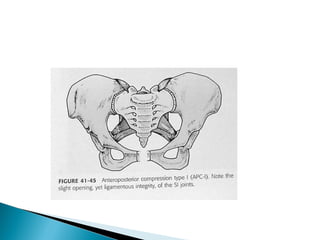

Anteroposterior compression Symphyseal diastasis or longitudinal rami

fractures

I.Slight widening of pubic symphysis or

anterior SI joint; stetched but intact anterior

SI, sacrotuberous and sacrospinous

ligaments; interat posterior SI ligament

 APC – I: Results from low to moderate energy

forces. The radiographic picture in one of slight

(< 2 cm) widening of pubic symphysis.